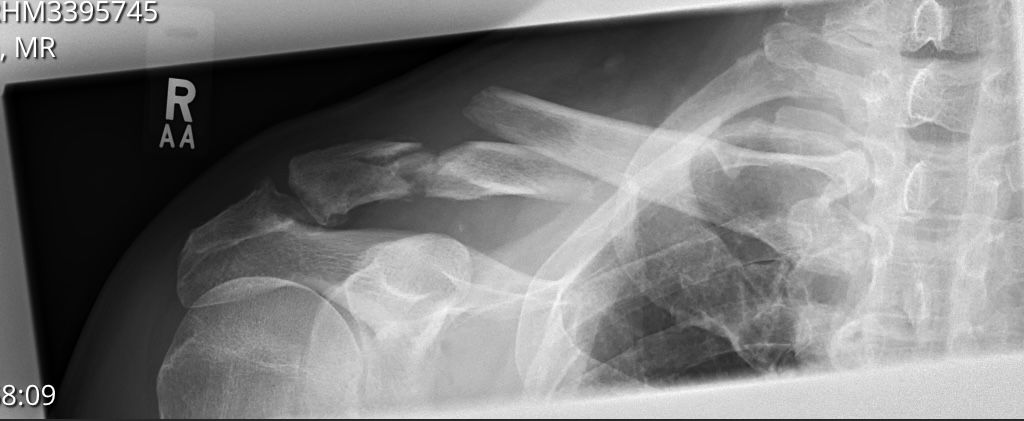

Here's my broken sticking out one.

Tried to stop a mate drink driving and he ran me over.

Zero cast or plate just a sling for a few weeks.

Took ages to heal and I couldn't sleep on that side for a year as it was sore.

Totally normal now apart from it sticking out like that. This was 20 odd years ago it happened.